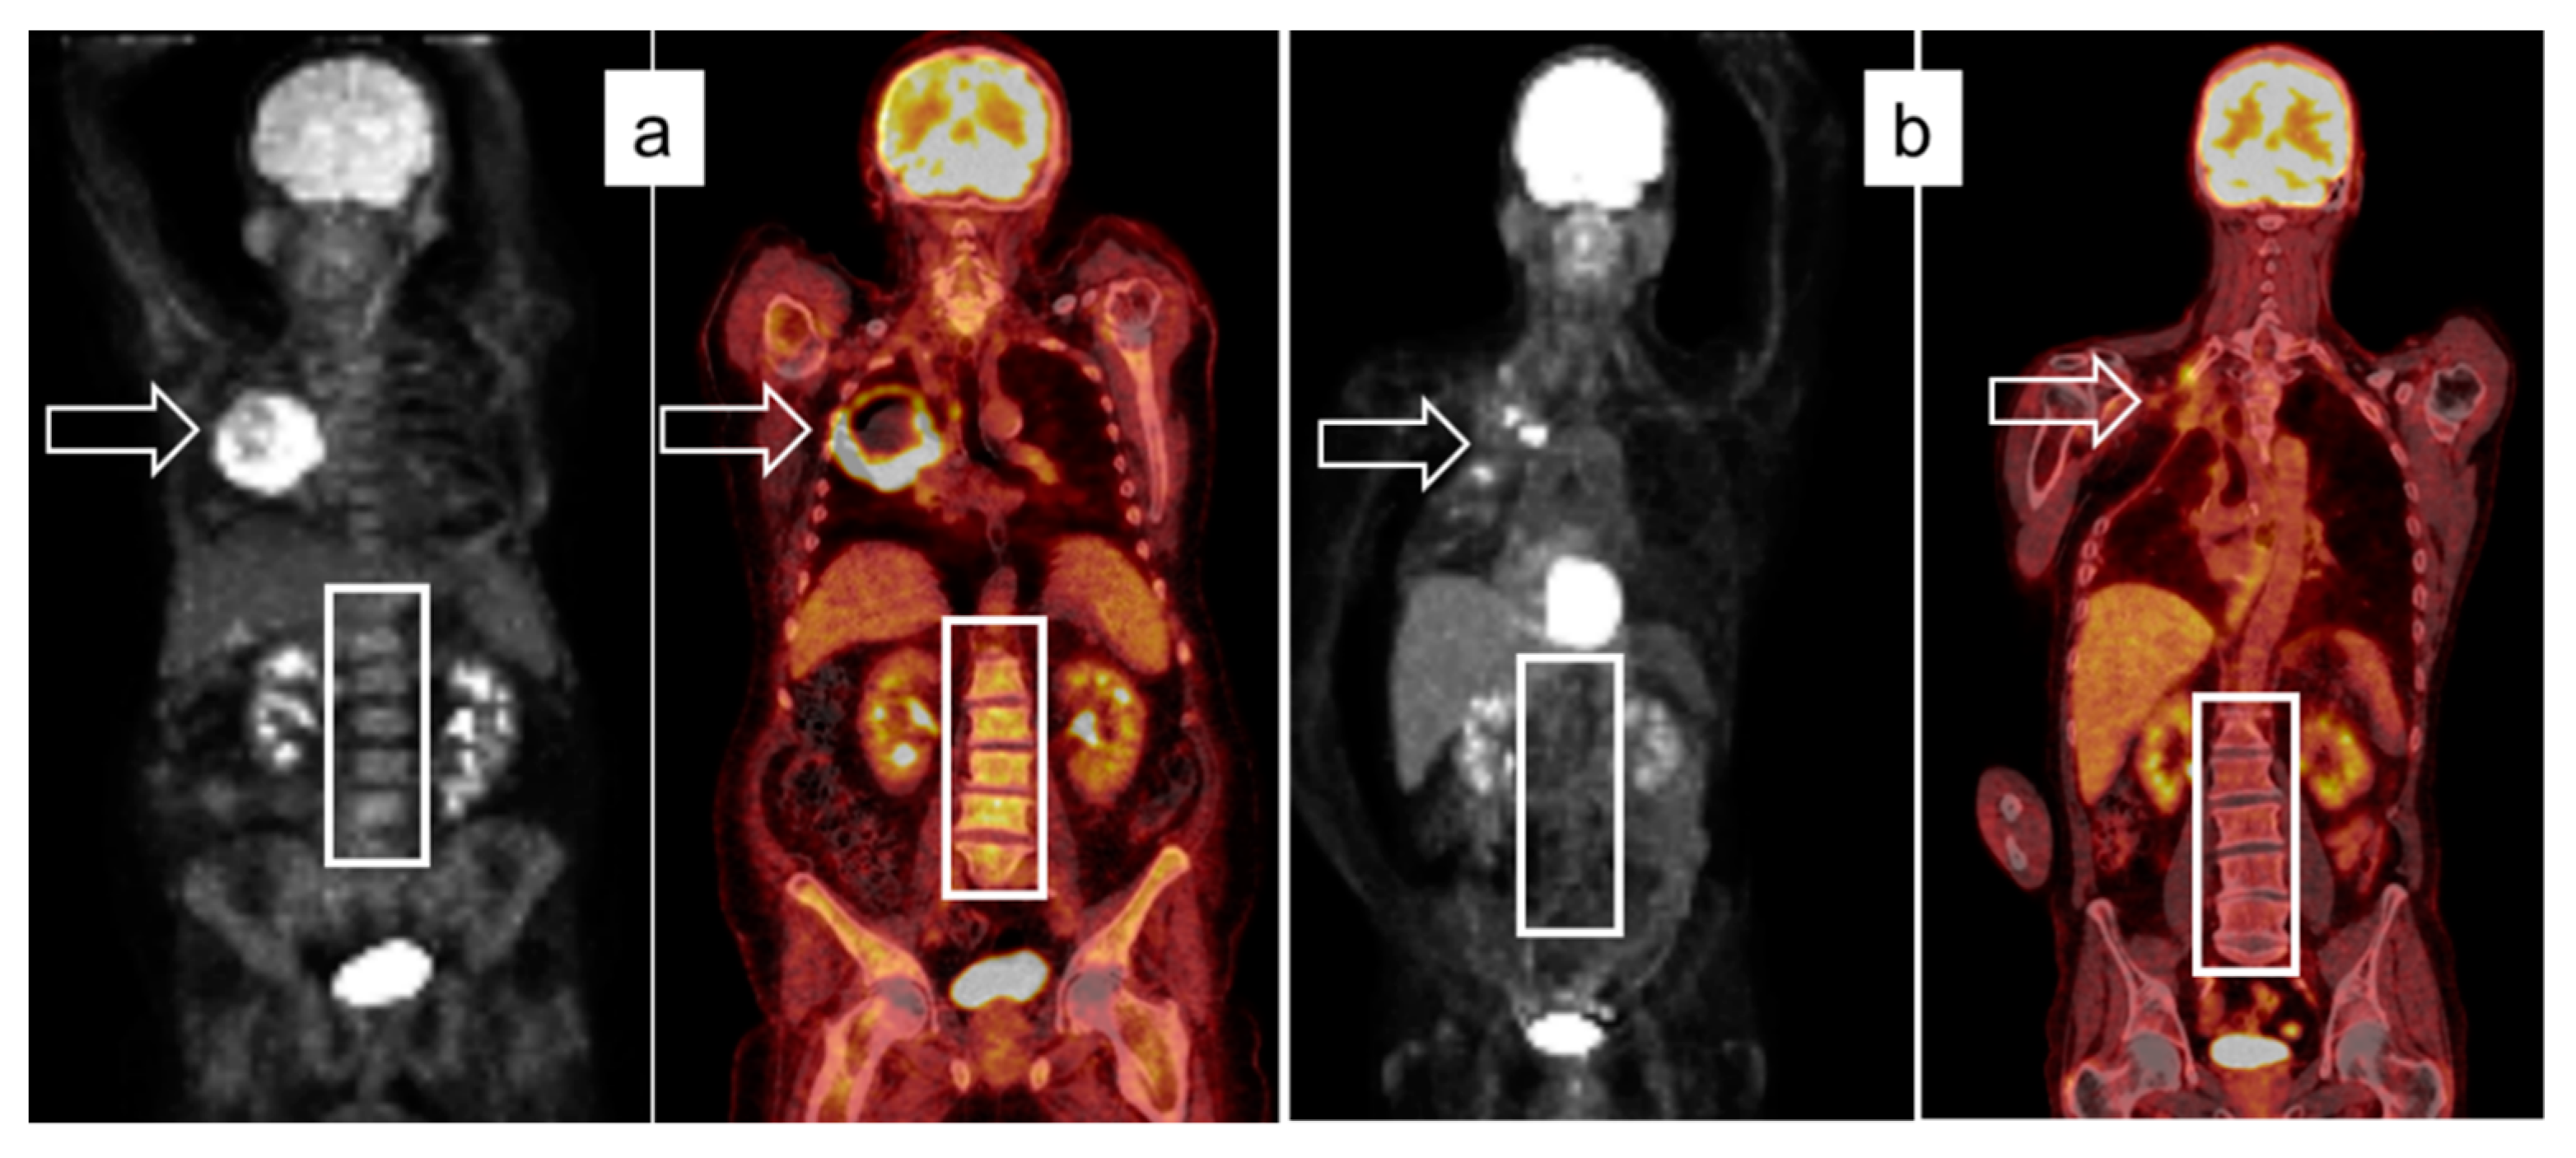

2.2. Image Acquisition Protocol and Analysis